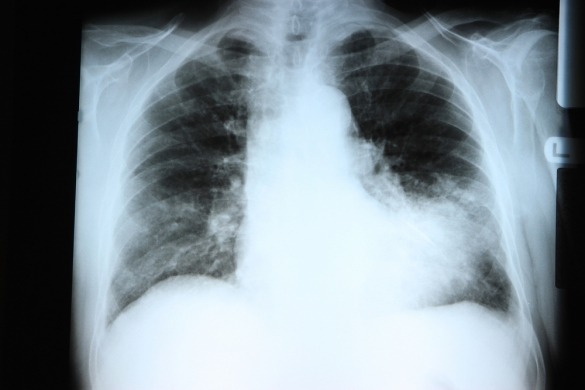

Les Européens peu conscients des risques que représente la pneumonie

En Europe, 3 millions de personnes sont atteintes de pneumonie chaque année et 1/3 d’entre elles doivent être hospitalisées. La pneumonie « communautaire » demeure ainsi l’une des causes les plus fréquentes de décès par infection en Europe. Les coûts pour la société liés au traitement de la pneumonie s’élèvent à près de 10 milliards d’euros chaque année. Paradoxalement, seuls 10% des adultes européens de plus de 50 ans sont actuellement vaccinés.